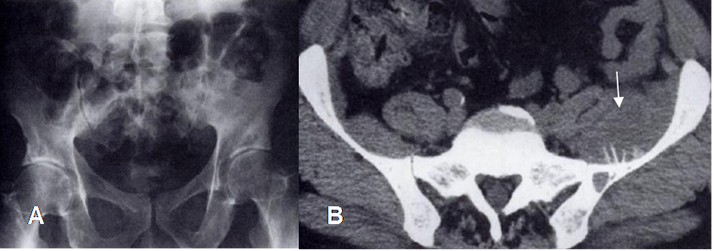

Fig 7 A. Tumor no visto en la pelvis.

A: Rx AP. Interposición de gas intestinal en la pelvis, que limita la valoración.

B: TAC axial. Lesión lítica del iliaco, con reacción perióstica y masa de tejidos blandos, por osteosarcoma, que no puede ser detectada en la Rx simple.